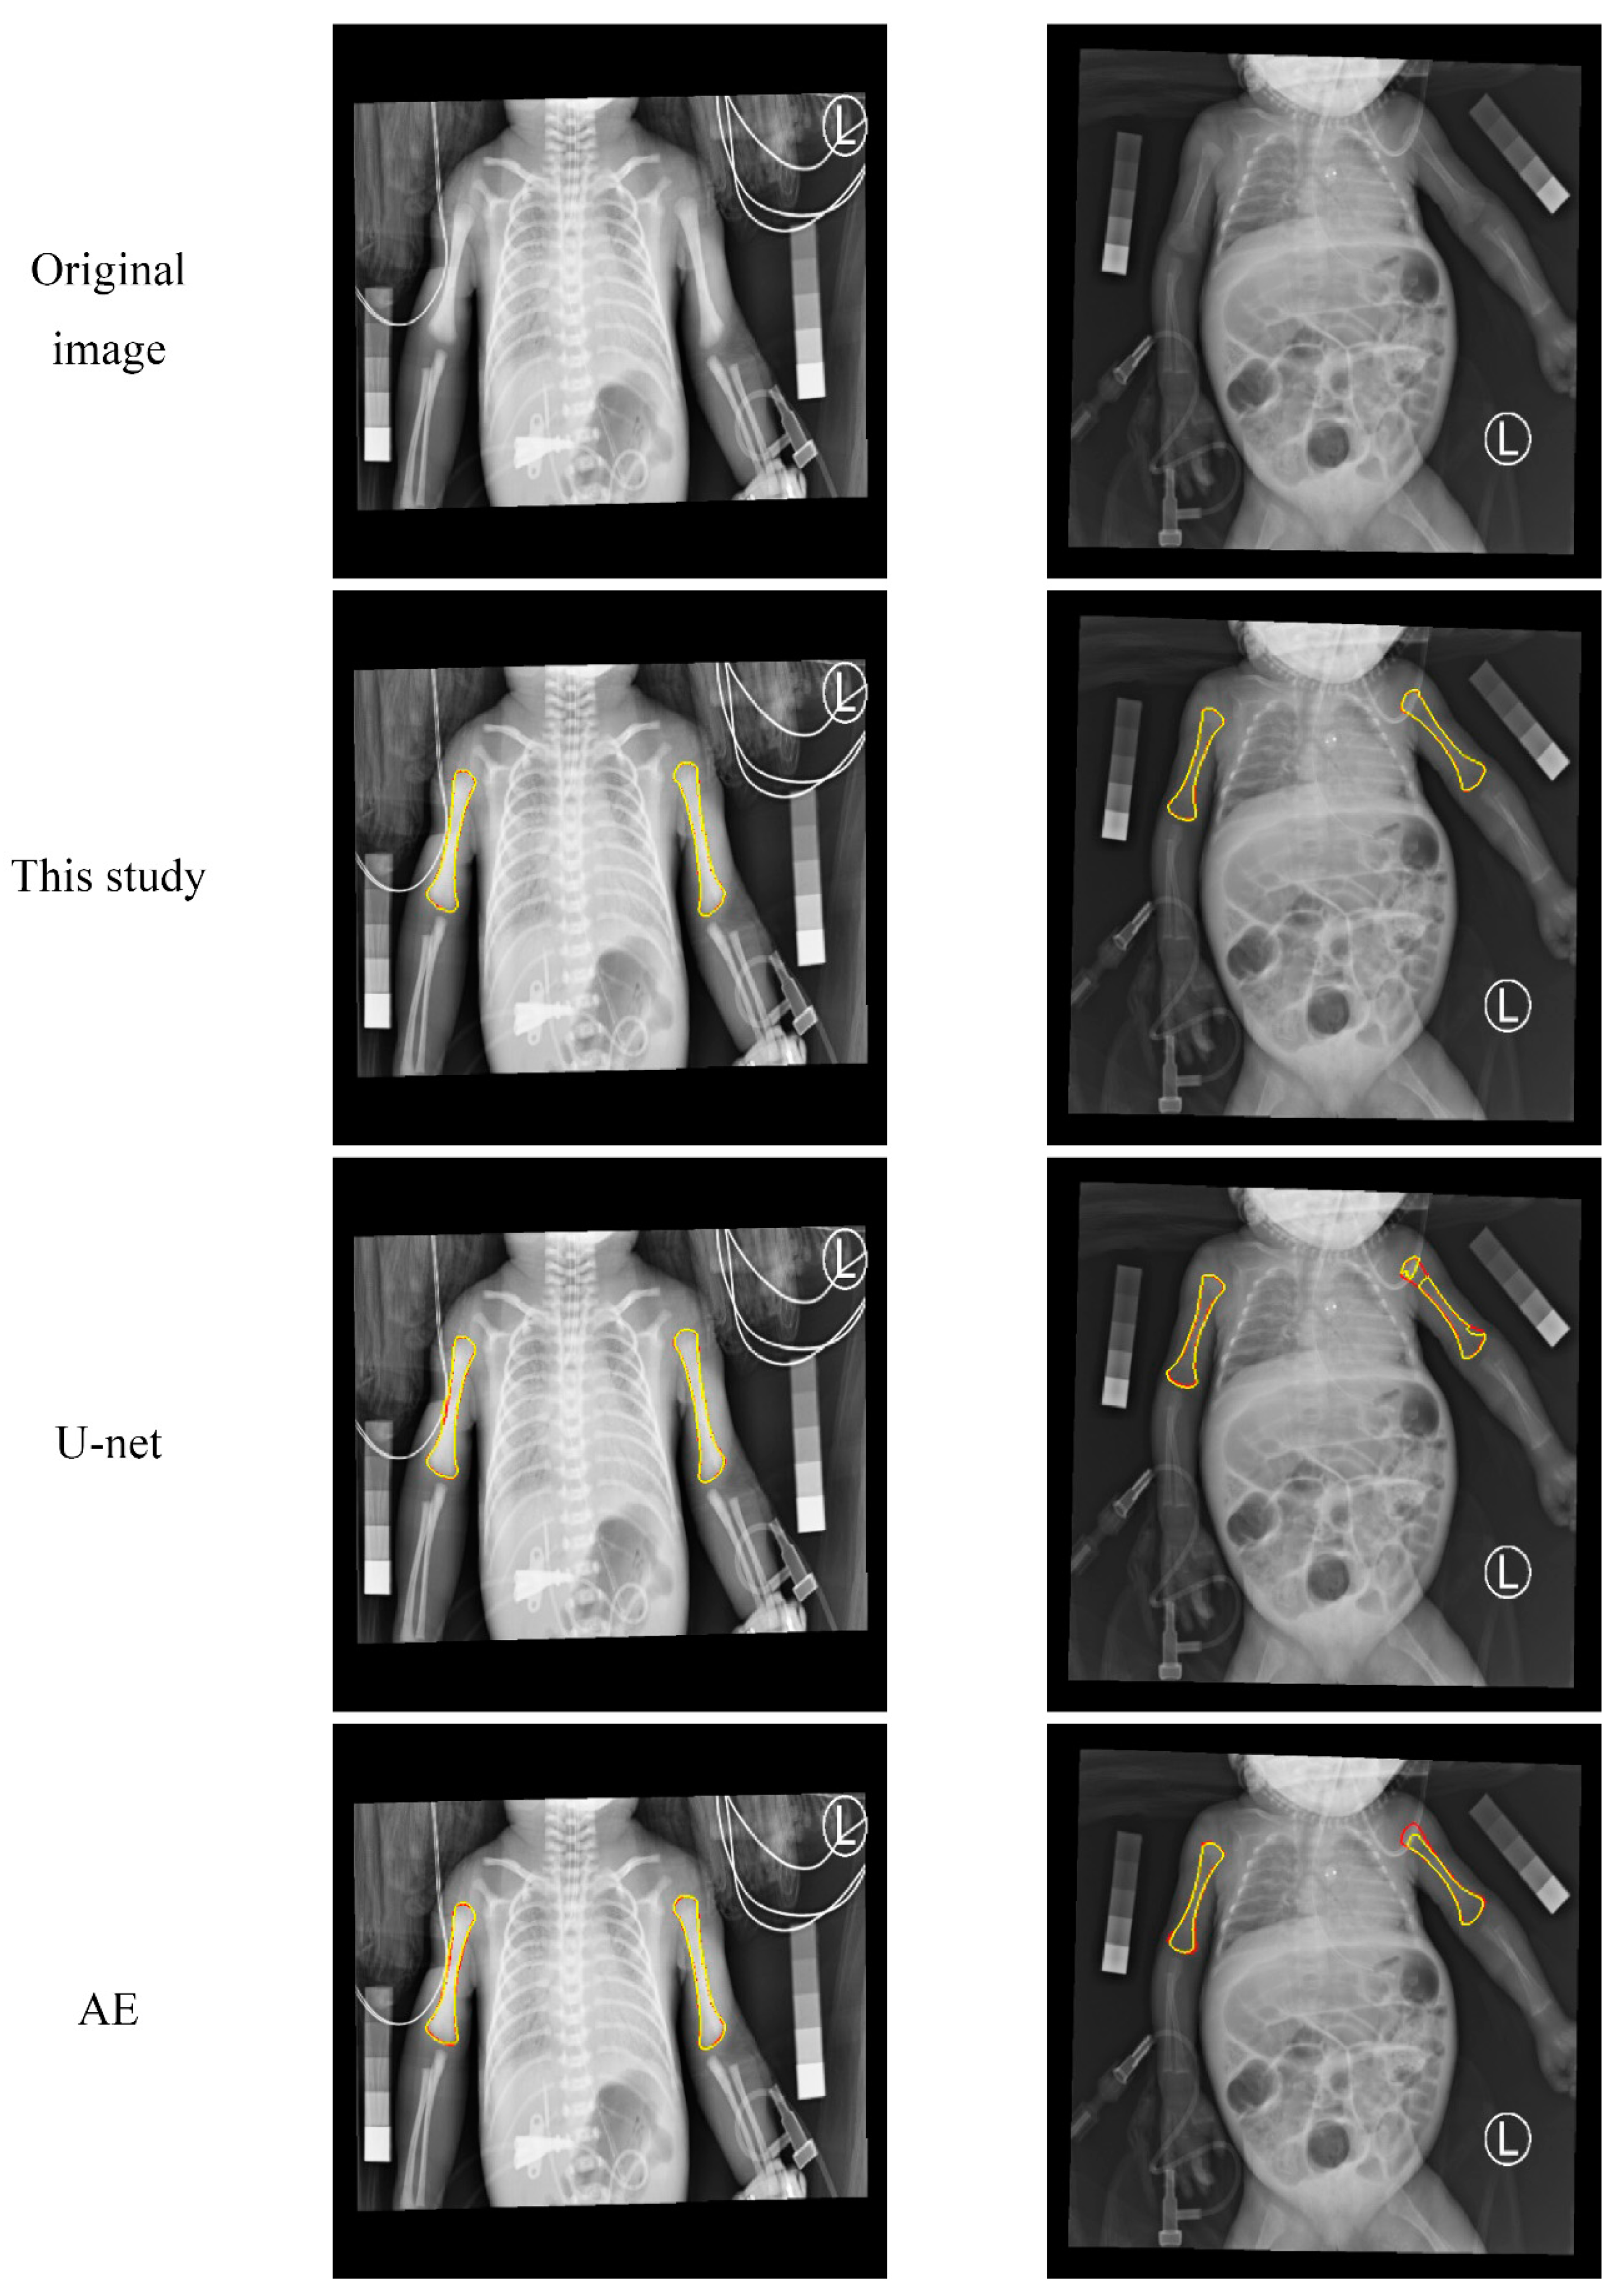

3.1. Qualitative Evaluation of the Humerus Segmentation